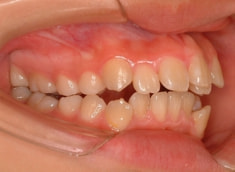

治療前